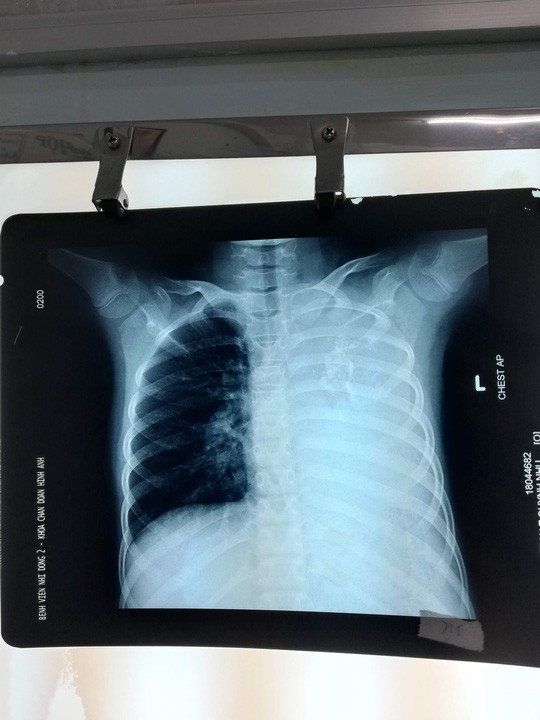

Bệnh nhi được người nhà đưa đến BV Nhi Đồng 2 khám do ho kéo dài, khó thở khi gắng sức. Qua hình ảnh CT scan ngực, các bác sĩ đã phát hiện một khối u phổi khổng lồ xâm lấn toàn bộ phổi trái gây tắc đồng thời phế quản gốc trái và động mạch phổi trái khiến bệnh nhi chỉ hô hấp bằng 1 phổi bên phải.

Bé gái mang khối u phổi khổng lồ nặng 1,5 kg ảnh 1

Khối u phổi trên phim XQuang - Ảnh: Người lao động